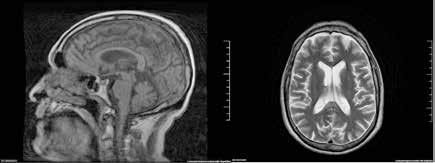

Ante la persistencia de la bradipsiquia y la dificultad para ejecutar órde nes moderadamente complejas, a pesar de que la madre decía que no veía grandes diferencias con respecto a su estado basal, se solicitó una resonan cia magnética cerebral. En la resonancia magnética se observó una altera ción de la intensidad de la señal en la porción central del cuerpo calloso, en concreto en esplenio y rodilla, con hiperintensidad en T2, hipointensidad en T1 basal y moderada restricción de la difusión; hallazgos que eran com patibles con el Síndrome Marchiafava-Bignami (Figura 3).

Se citó nuevamente en la consulta de Medicina Interna, apreciándose cierta mejoría subjetiva a nivel cognitivo, ganancia ponderal (64 kg) y difi cultades para la marcha. En la RMN solicitada meses después no se observó mejoría alguna, sino una progresión de la enfermedad con aparición de necrosis, atrofia y aumento de difusión en el esplenio del cuerpo calloso (Figura 4).

Figura 3.

Resonancia magnética. Secuencia T1 y T2. Cortes sagital y transversal. Estudio artefactado por el movimiento del paciente. Estudio T1 donde se aprecia una lesión hipointensa con moderada restricción a la difusión en las capas medias del esplenio del cuerpo calloso, que en la secuencia T2 corresponde con una lesión hipertensa. Esta lesión en dicha localización y en el contexto clínico del paciente es altamente sugestiva de Marchiafava-Bignami.

Figura 4. Resonancia magnética cerebral a los 8 meses. Secuencias T1, T2 y difusión, corte sangital y transversal. En el esplenio del cuerpo calloso se observa adelgazamiento, con presencia de un área de necrosis en las capas medias de hiperintesidad de señal periférica con aumento de difusividad. En comparación con RM previe se objetivan cambios evolutivos con necrosis, atrofia y aumento de la difusión. Hallazgos compatibles con la enfermedad de Maarchiafava-Bignami.